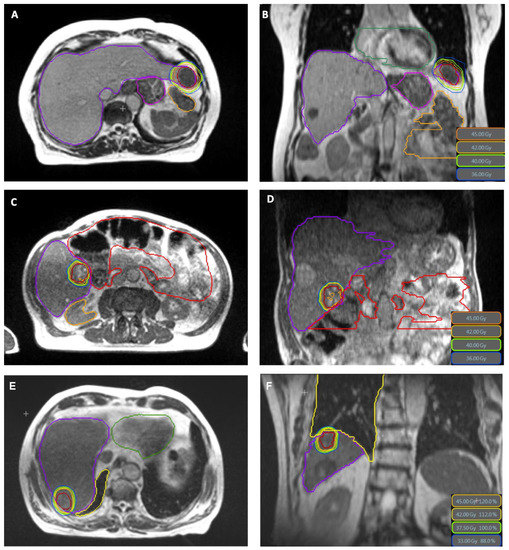

Treatment characteristics are shown in Table 2. Across all patients, 15 lesions were treated in a total of 47 fractions, with a median PTV prescription dose of BED10 84.4 Gy in 3 to 5 fractions (range 59.5–112.5 Gy). The mean GTV BED10 was in median 147.9 Gy (range 71.7–200.5 Gy). In two patients, two lesions were treated simultaneously with the same isocenter, in one patient two lesions were treated simultaneously with two isocenters and in one patient a second hepatic lesion was treated sequentially. The contrast agent Gadoxetic acid was applied in 38.4% of patients. Online-adaptive planning was performed in 46 of 47 fractions (97.8%). The median PTV volume was 39.11 cm3 (8.3–411.3 cm3) and the median liver volume was 1242.5 cm3 (range 879.6–2625.3 cm3). The median liver dose was 5.6 Gy (range 2.8–15.5 Gy). Treatment plans were created using a median number of 11 beams (range 7–16), 33 beam segments (range 9–60) and 3367 monitor units per fraction (range 1503–6776), respectively. Examples of treatment plans are shown in Figure 1. The calculated median delivery time from the TPS was 13.07 min (range 6.57–23.41 min) and net median beam-on time was 10.49 min (range 4.03–20.59 min). The overall treatment duration, including the adaptive workflow and treatment delivery using respiratory gating was in median 53 min (range 46–78 min). Unintended treatment interruptions during the application of a fraction occurred in 11 of 47 fractions (23%), but all fractions were completed with no delay within the same treatment session. These interruptions occurred when there was a technical error or when there were difficulties with gating applicability (e.g., the patient could not reach the BH level due to intrafractional motion), which required repositioning of the patient through a couch shift, or when there were difficulties with the anatomical tracking algorithm (e.g., low correlation), which required a manual adjustment of the tracking structure.

Figure 1.

MR-based plans in axial and coronar plane (GTV in red color) with sparing of small bowel (orange), stomach (pink) and heart (green) in (A,B) and small bowel (red) in (C,D). (E,F) show the plan of the patient who suffered a duodenal perforation, with a clear distance between the treated volume and the duodenum. The PTV dose in this case was 37.5 Gy in 3 fractions prescribed to 65% isodose, GTV Mean BED10 was 146.7 Gy.

The oMRgRT treatment was completed successfully in all patients and was very well tolerated. Overall, six patients reported mild acute toxicity, of which six patients reported CTCAE grade one nausea, two patients vomiting grade one, two patients fatigue grade one and one patient diarrhea grade one. No CTCAE grade two toxicity was observed. One patient died shortly after completion of radiotherapy of a metastasis of a colorectal carcinoma in liver segment VII due to a peritonitis as a result of a duodenal perforation. Radiation plans were retrospectively evaluated and a relationship with the irradiation could be excluded, as the localization of the perforation was not close or within the irradiation area of the treatment (see Figure 1E,F). However, this patient had a prior systemic treatment with bevacizumab. For six patients data was available to calculate pre- and post-treatment Child-Pugh-Score. The value was unchanged in all patients except the one who developed the peritonitis.